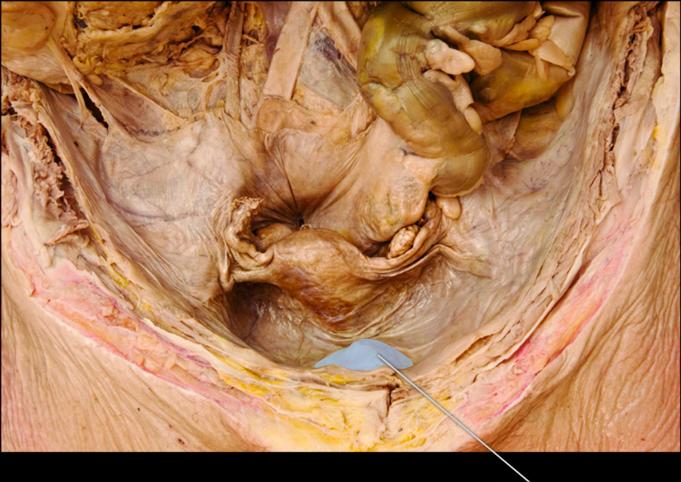

Identify the highlighted uterine layer.

Myometrium

Which hormone stimulates contraction of the highlighted layer? (Myometrium)

Oxytocin

The highlighted structure is derived from which membrane?

Peritoneum

Identify the highlighted structure.

Left Uterine Tube

Identify the highlighted structure.

Ovary